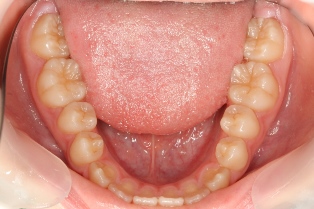

14歳の妹さんです。お姉さんと同じく園児の時からメインテナンスに来ています。これこそが歯科医療のゴールであり、患者さんと術者の win-win の関係ではないでしょうか。健康なのですが健康維持のためのメインテナンスです。